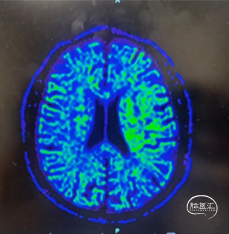

T1

T2 Flair

重要影像结论:头MRI示:1、脑干、左侧小脑、双侧额顶叶、双侧颞叶、双侧岛叶、胼胝体、右侧丘脑、双侧基底节区、双侧放射冠区、双侧半卵圆中心、双侧侧脑室周围多发腔隙性脑梗死、缺血灶,部分软化灶伴胶质增生。2、脑白质病变、双侧大、小脑萎缩。